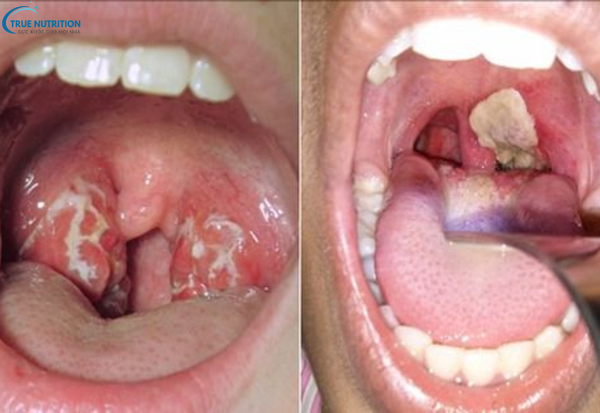

- Màng giả ở họng: Một triệu chứng rất đặc trưng của bệnh bạch hầu là sự hình thành lớp màng giả trong họng. Màng này có màu xám hoặc trắng ngà, giống như váng sữa hoặc màng nhầy, bám chặt vào niêm mạc họng. Màng giả này có thể lan rộng từ họng xuống khí quản và thanh quản, gây tắc nghẽn đường thở và gây khó khăn trong việc hô hấp. Khi màng này bị cào ra, có thể để lại vết loét và chảy máu.